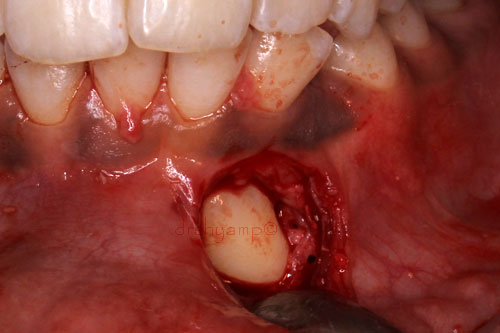

Removal of impacted canine